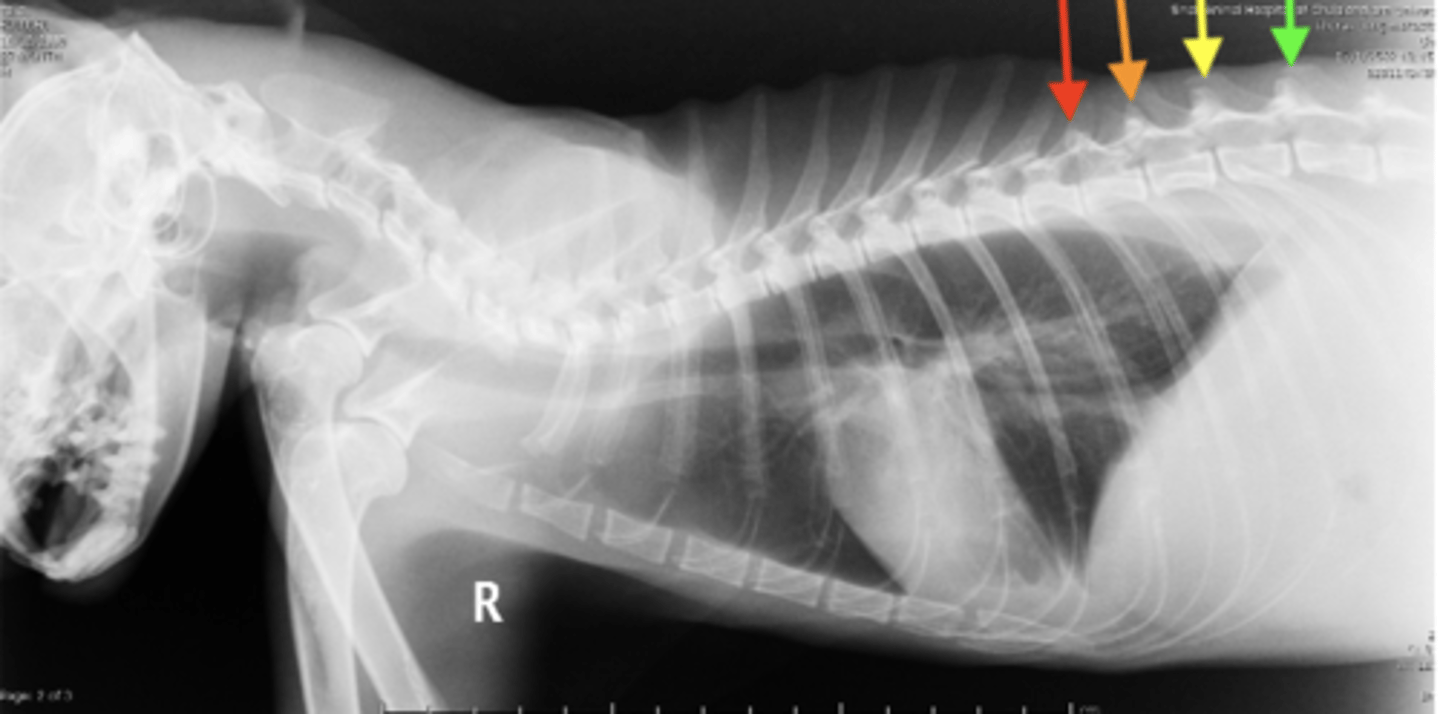

The anticlinal vertebra can be used as a landmark in _________ of the thorax. Why?

yellow arrow

Where on this radiograph is the anticlinal vertebra?